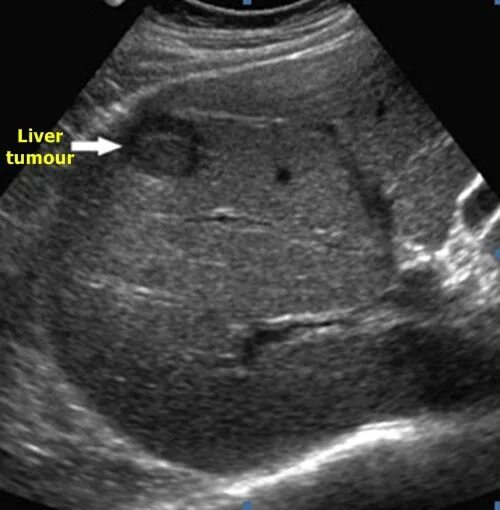

Узи шип